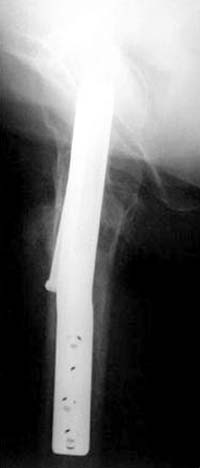

>Винты немного вертикальнее провести и было бы красивее

Правильная техника фиксации - это три параллельных каннюлированных винта под углом 130 -135 градусов к диафизу, не ниже уровня малого вертеля. Проведенные ниже вертела винты с бОльшим углом (более вертикальные) в 20% осложнялись подвертельными переломами бедра. Ближе к кортикальному слою винты с длинным контактом резбовой части, а также каннюлирванные механически лучше, чем сплошные. Расположение винтово - в в виде V т.е. один внизу по калькару и два сверху-спереди и сзади.

Burstein AH and Wright TM: Fundamentals of Orthopaedic Biomechanics. Williams & Wilkins, Baltimore, pp. 160-169, 1994

Для убедительности здесь пример подвертельного перелома после 3 недели, где латеральный кортекс ослаблен еще и из-за неоднократных попыток введения шурупов.